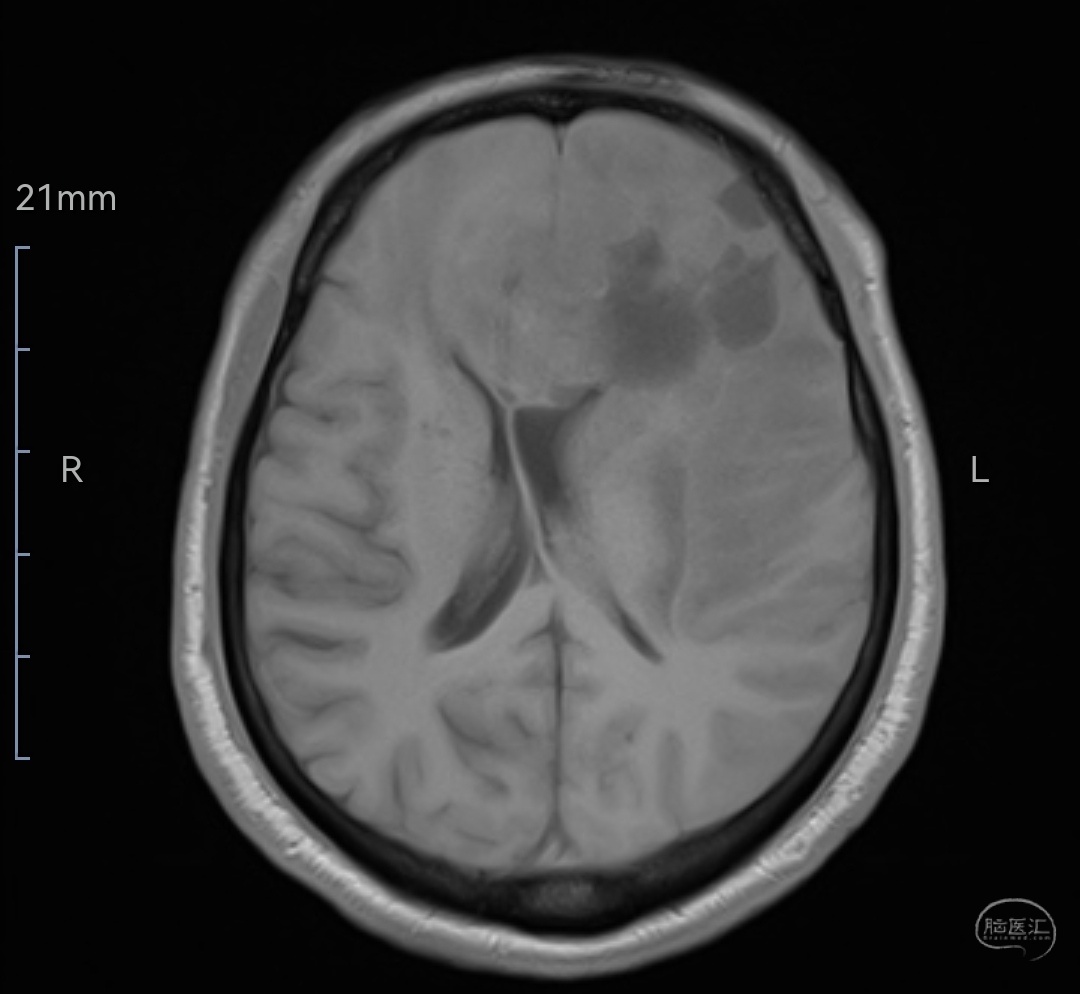

MRIT1相轴位示肿瘤等信号,位于双侧额叶,左侧为主,已侵犯至胼胝体嘴、膝部及左侧颞岛叶